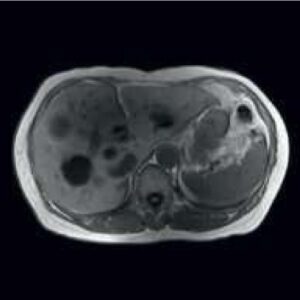

Body Imaging

The Body Suite is specialized for Clinical body examinations.